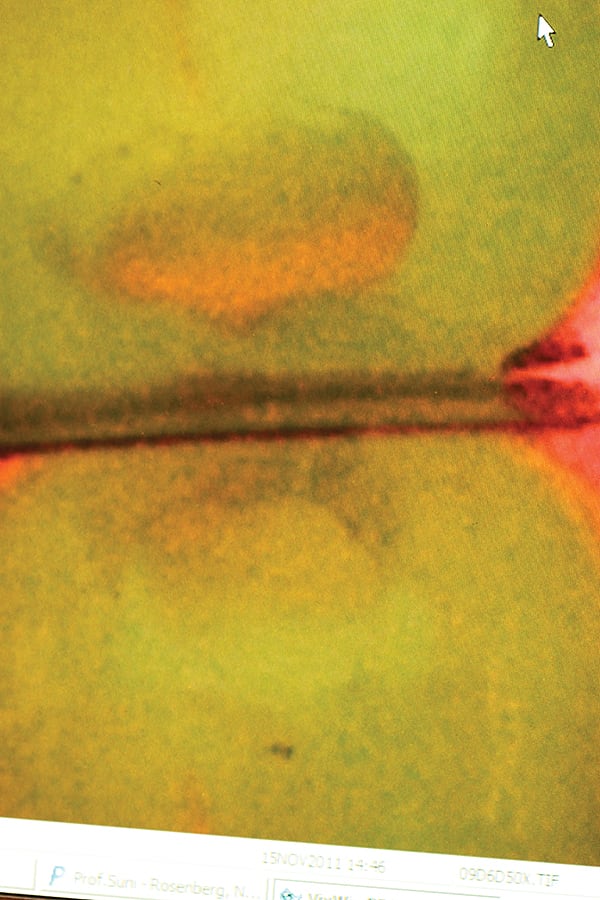

2. A caries detection camera (Spectra, Air Techniques Inc., www.airtechniques.com) was used to detect decay that was still present, which is noted by the red hue on green image.